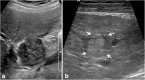

Malignancies of the biliary tract include cholangiocarcinoma, gallbladder cancers and carcinoma of the ampulla of Vater. Biliary tract adenocarcinomas are the second most common primary hepatobiliary cancer. Due to their slow growing nature, non-specific and late symptomatology, these malignancies are often diagnosed in advanced stages with poor prognosis. Apart from incidental discovery of gall bladder carcinoma upon cholecystectomy, early stage biliary tract cancers are now detected with computed tomography (CT) and magnetic resonance imaging (MRI) with magnetic resonance cholangiopancreatography (MRCP). Accurate characterization and staging of these indolent cancers will determine outcome as majority of the patients' are inoperable at the time of presentation. Ultrasound is useful for initial evaluation of the biliary tract and gallbladder masses and in determining the next suitable modality for further evaluation. Multimodality imaging plays an integral role in the management of the biliary tract malignancies. The imaging techniques most useful are MRI with MRCP, endoscopic retrograde cholangiopancreatography (ERCP), endoscopic ultrasound (EUS) and positron emission tomography (PET). In this review we will discuss epidemiology and the role of imaging in detection, characterization and management of the biliary tract malignancies under the three broad categories of cholangiocarcinomas (intra- and extrahepatic), gallbladder cancers and ampullary carcinomas.